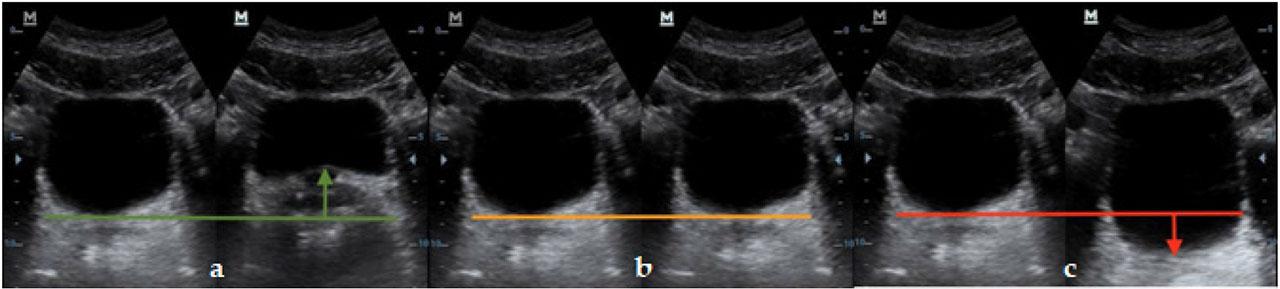

The patients who underwent the examination were asked to contract and release their pelvic floor muscles before the examination. During the examination, the patient performed multiple trial attempts at contracting and releasing the pelvic floor muscles while the ultrasound array transducer was moved to obtain the highest possible quality image. This approach made it possible to assess the position of the pelvic floor during contraction. Correct muscle function was indicated by elevation of the pelvic floor muscles during volitional contraction (Figure 2a); conversely, a lack of reaction to the contraction, or depression, was assessed as incorrect function (Figure 2b and 2c, respectively).

The position of the pelvic floor during contraction: (a) Elevation of the pelvic floor muscles during volitional contraction; (b) Lack of reaction of the pelvic floor muscles during volitional contraction; (c) Depression of the pelvic floor muscles during volitional contraction